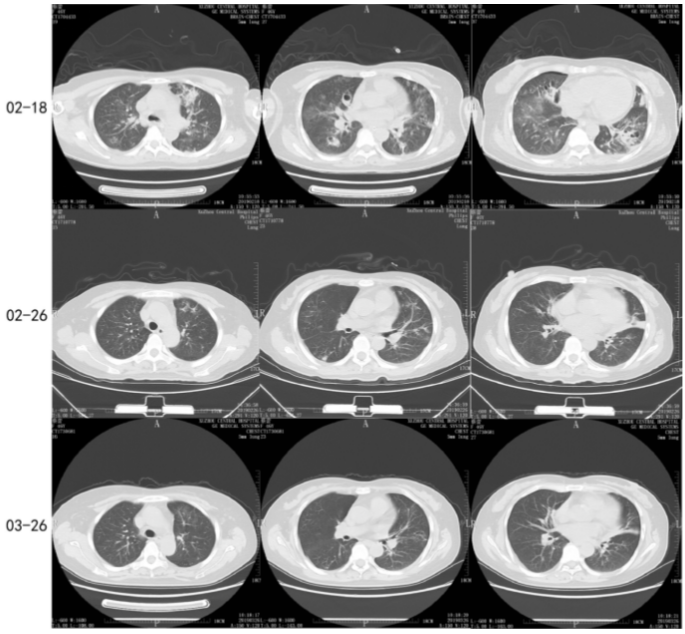

第13天(2月18日),患者体温正常,气道吸出痰液较前减少,呼吸循环等生命体征稳定,呼吸机支持条件不高,复查感染指标较前下降,复查肝功能较前好转:ALT 128.0 U/L,AST 43.0 U/L,ALP 87 U/L,GGT 142 U/L。再次评估胸部CT示:较2月11日右肺下叶病变稍有吸收(图2)

第21天(2月26日),患者体温正常,时有咳嗽、咳少量黄白痰,伴声音嘶哑,无明显憋喘,两肺听诊呼吸音稍粗,左下肺可闻及少许啰音,复查胸部CT示两肺病变较前好转(图2)

近1个月后(3月26日)患者返院随诊,未诉不适,复查胸部CT示:两肺炎症较2月26日吸收、减少(图2)

图2  胸部CT图像(2月18日、2月26日、3月26日)